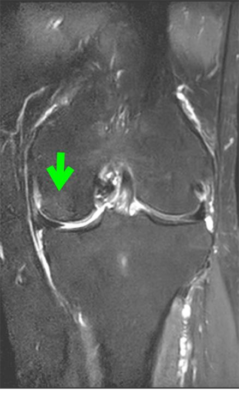

4か月後フォローMRI(改善例)

治療(体重を減らす、装具・杖の使用など)で、

MRIの変化が軽くなり、痛みが改善する例があります。

※回復のスピードや程度には個人差があります。

治療後。骨の炎症は改善しています。

治療後、壊死部の圧壊は免れました。壊死巣は傷として残りましたが、痛みはありません。